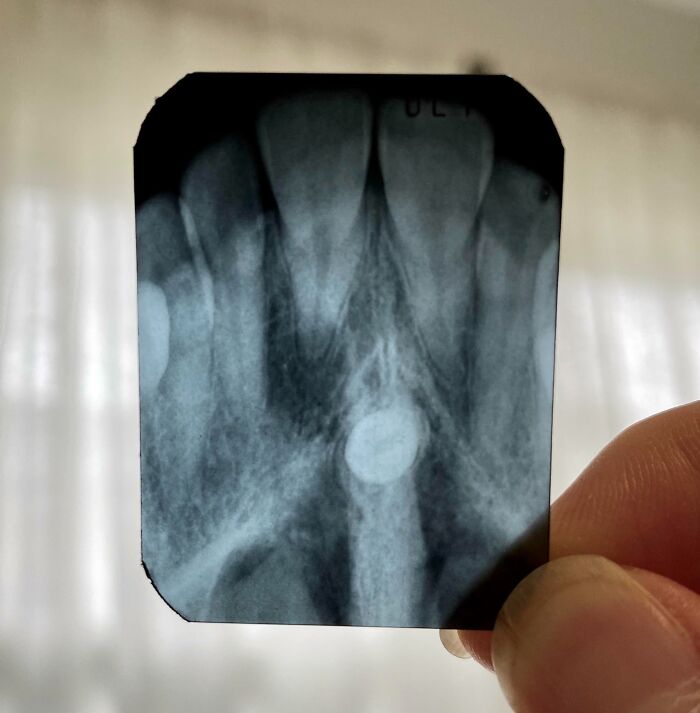

My 6-Years-Old's Dental X-Ray